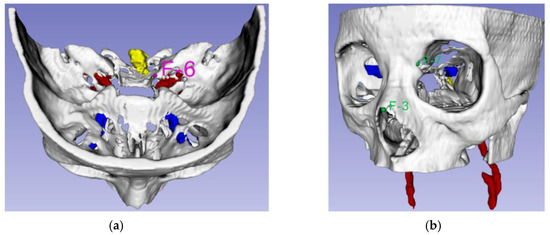

3.2. Registration for Construction of Navigation System

4. Design of the Bendable Endoscope, Surgical Tool and Phantom Design